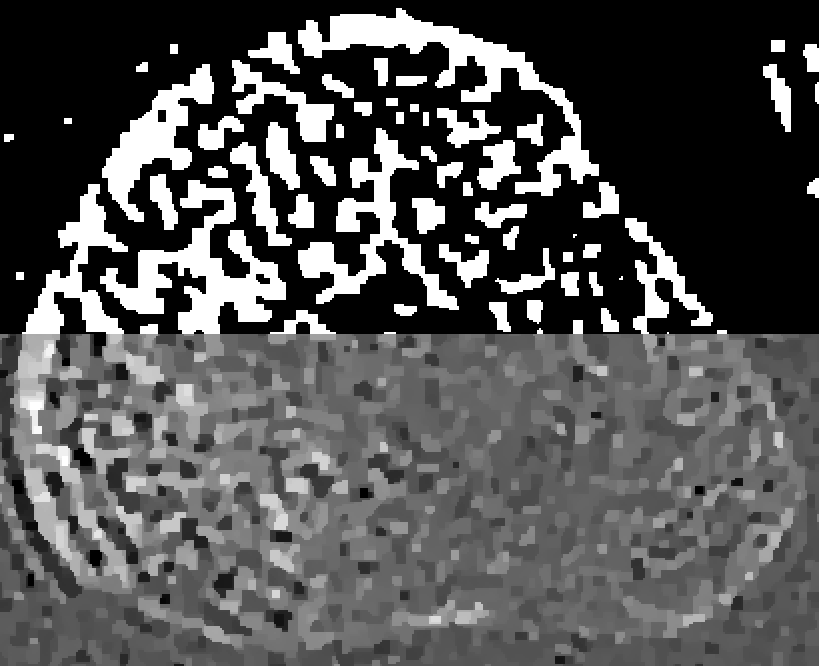

Refer to captionID blurfullRefer to captionshort-1Refer to captionshort-2Refer to captionSI blurRefer to captionRefer to captionRefer to captionSV blurRefer to captionRefer to caption0.0000.0150.0300.0450.060

Figure 4: Reconstructions of the medial bone with the highest mutual overlap over all thresholds and β𝛽\beta’s. The top half of each reconstruction is thresholded.

Figure 4 shows the medial-bone reconstructions (bottom of each image) and segmentations (top of each image) corresponding to the best possible mutual overlap (optimal threshold and β𝛽\beta values) with each scan type and blur model combination. All SV reconstructions depict more trabecular structure than the shift-invariant (SI) or ID models. The difference in image quality among ID reconstructions is readily apparent in these images, with the short-1 scan resulting in the most trabecular detail. Finally, the SI images depict more detail than the ID model but less detail than the SV reconstructions. However, the SI model results in a ringing artifact, particularly evident on the lower left aspect of the medial bone in the full scan reconstruction. This is likely due to blur/model mismatch (the SI model is accurate at the center of the detector but less accurate at the edges).